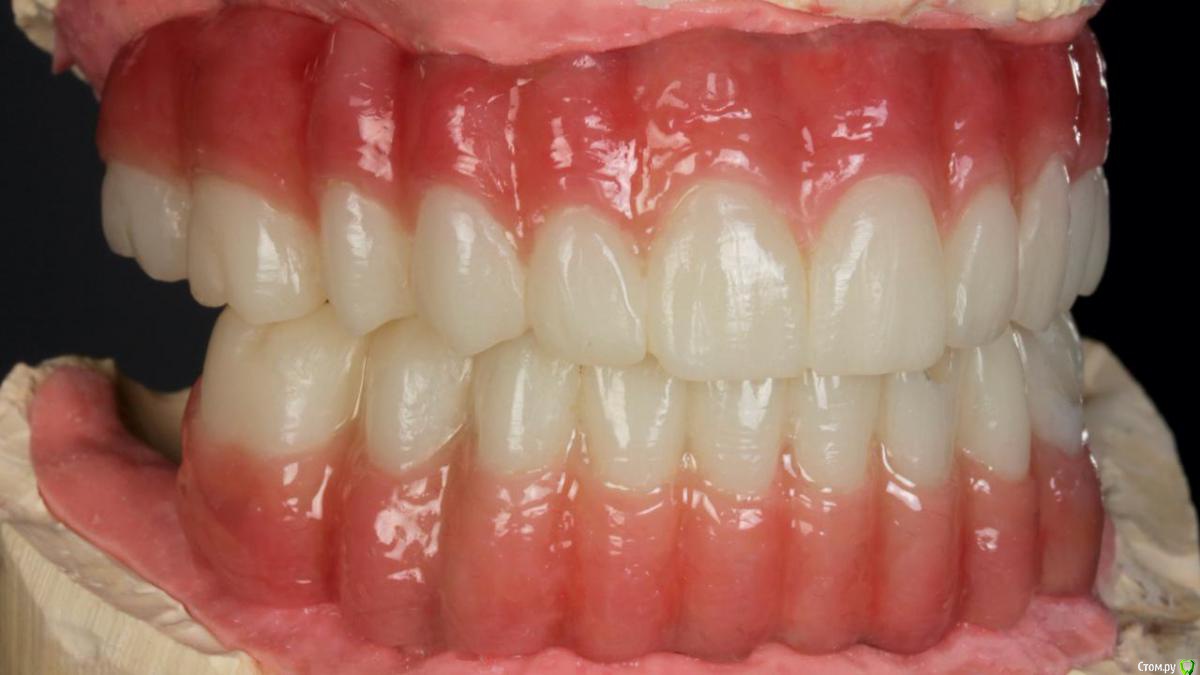

Bier Опубликовано 10 февраля, 2020 Поделиться Опубликовано 10 февраля, 2020 Хирургия в седации 3,5 часа + редукция гребня. По шаблону под пилот. Все мультиюниты были заранее выбраны техником и четко сели.Временные армированные протезы (лазерное спекание) 8 Ссылка на комментарий